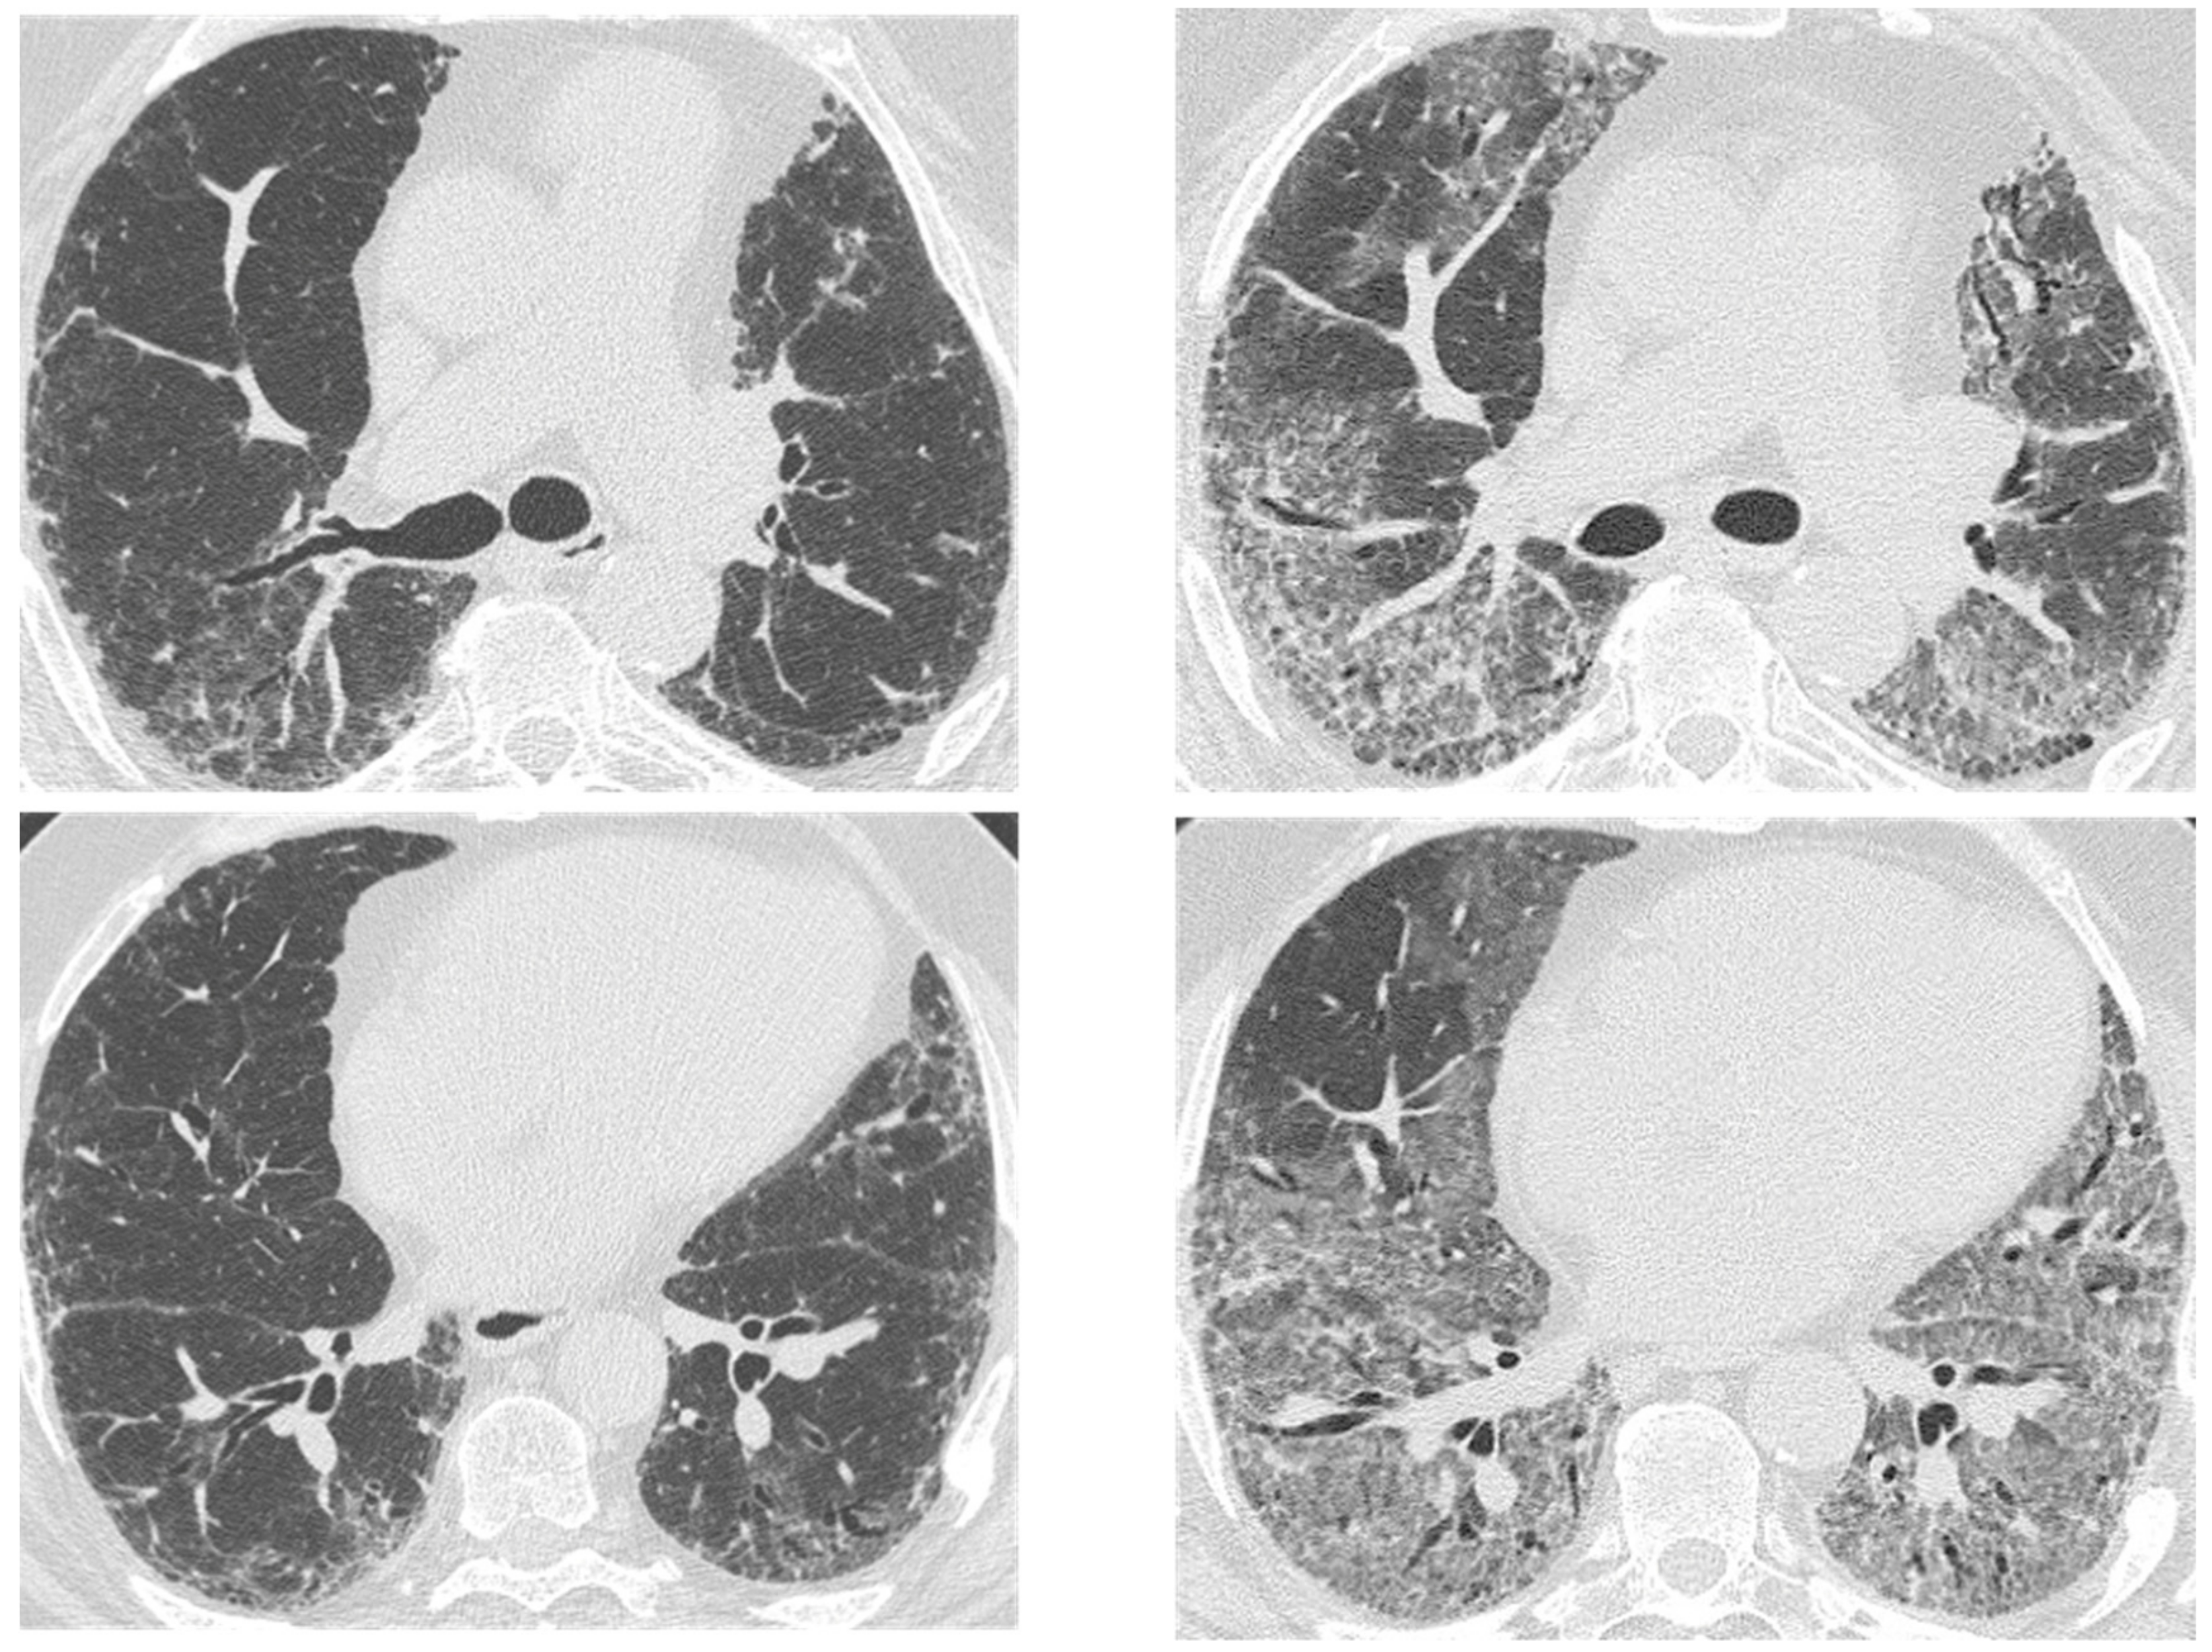

| Acute | Infections | Mycobacterium species | Peripheral mass-like lesion/subpleural nodules/segmental or lobar coalescent consolidation with or without necrotising cavitation. |

| Pneumocystis jirovecii | Ground glass opacity/no change from the baseline in a clinic context of infection. | ||

| Aspergillus | Fungal fronds in a pre-existing cavity in early stages. Subsequent coalescence of the cavity (air crescent sign). | ||

| Acute exacerbation IPF | New bilateral ground glass opacities and/or consolidation on a background of reticular or honeycombing pattern. | ||

| Right heart failure | Profuse septal thickening, ground glass opacities, pleural effusion on a background of reticular or honeycombing pattern. | ||

| Chronic | Lung cancer | Ill-defined rounded lesion, mimicking air space consolidation/nodular lesion developing within peripheral and basal honeycombing areas. Ground glass opacity in fibrosis area (mucinous bronchioloalveolar carcinoma). | |